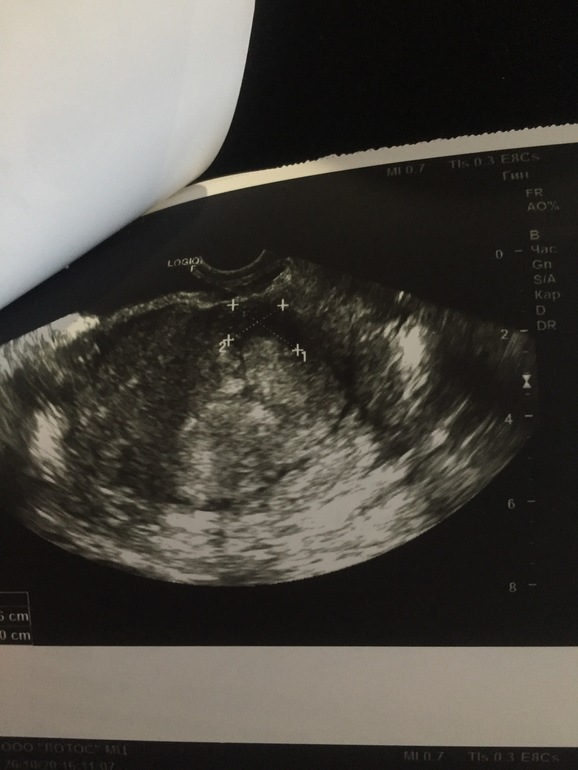

УЗИ 8-9нед

Гематома только что. Но это заживает с грамотным лечением. На вашем сроке они у многих возникают.